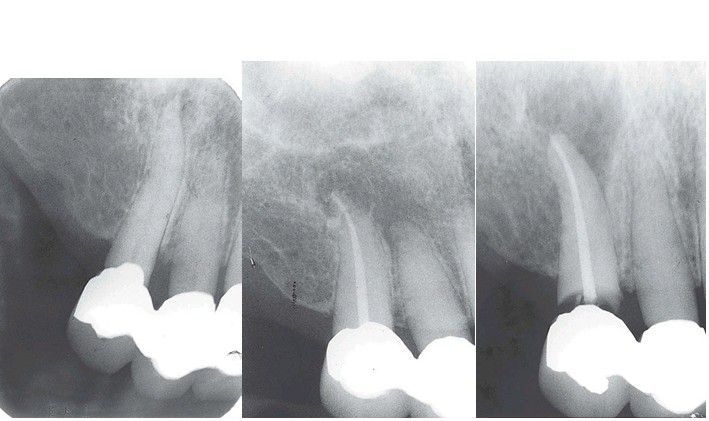

Four years after endodontic therapy, the patient complained of pain and swelling associated with tooth #6. The initial impression was that apical surgery was indicated. however, further radiographs revealed the true cause of the endodontic failure. The initial endodontic access through the crown or caries damaged the coronal seal and recurrent decay followed.